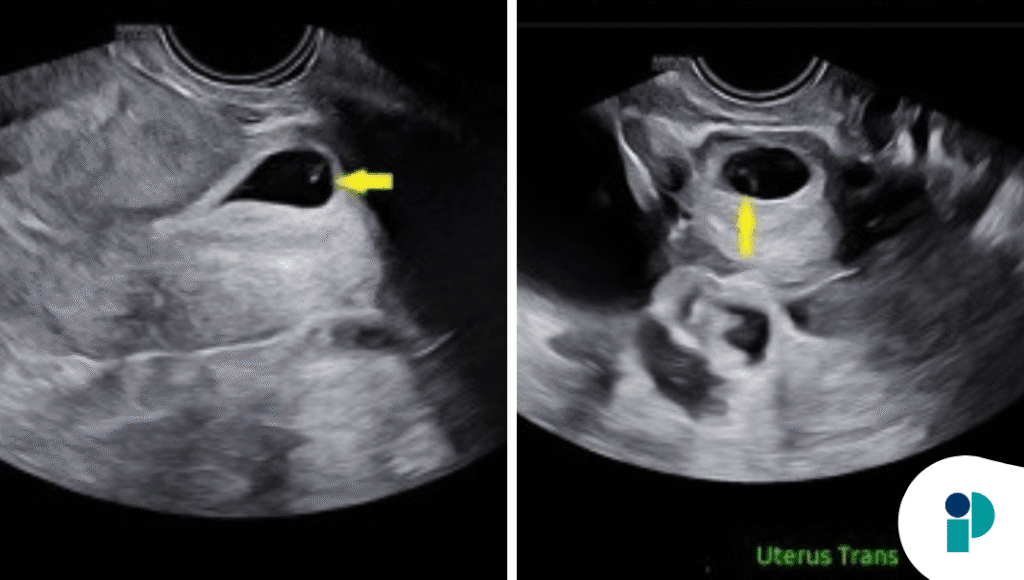

Se reporta el caso de una paciente de 36 años, con dos cesáreas transversales bajas previas, que acudió en el primer trimestre de gestación. Una ecografía confirmó el diagnóstico de PECES tipo 2.